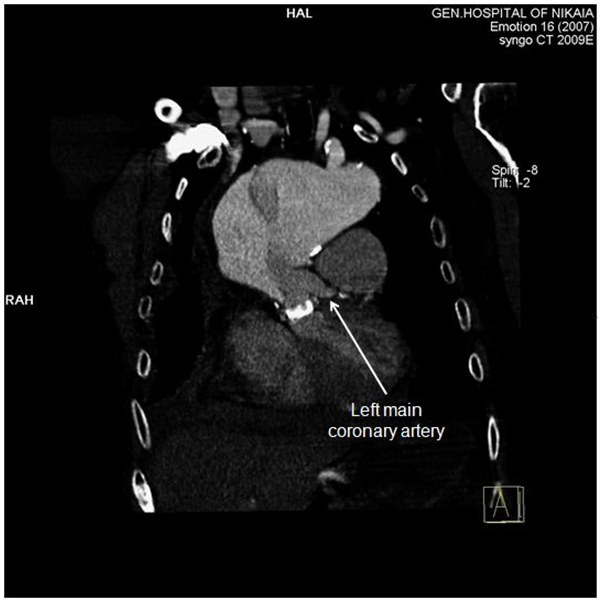

Figure 5 CT-angiography, anterior frontal view: Left main coronary artery is clearly demonstrated, while right coronary artery is compromised by the aneurysm.